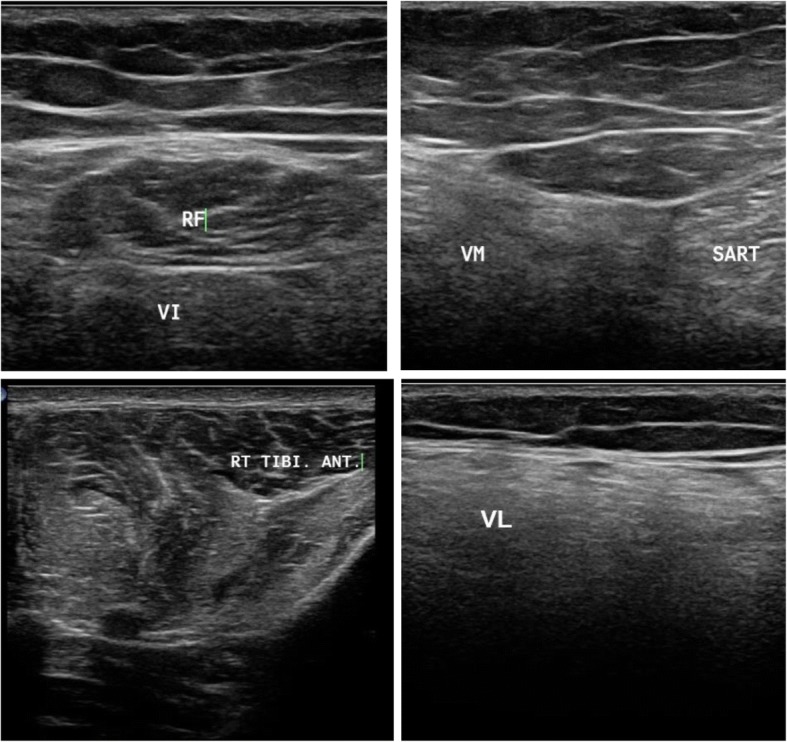

Fig. 4.

Muscle ultrasound in patient suspected to be with acid maltase deficiency showing affection of the vastus intermedius (VI) and sparing of the rectus femoris (RF) and vastus lateralis (VL) and affection of the vastus medialis (VM) with sparing tibialis anterior (TA)